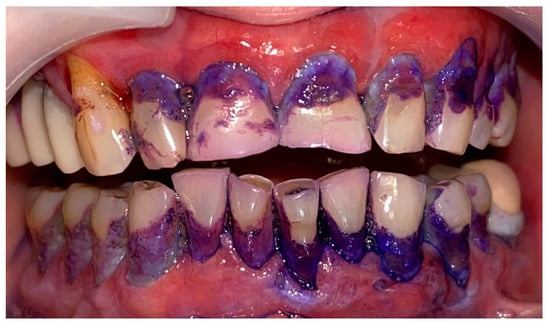

2. Materials and Methods